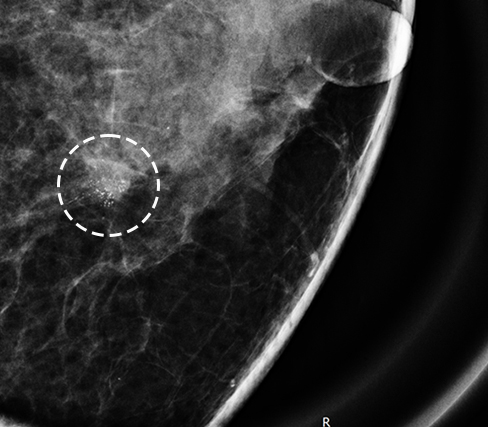

군집성 미세석회화

* 미세석회화: 0.5mm 이하로 작고 단위면적당 입자수가 많으며 크기와 모양이 균일하지 않음

* 군집성 미세석회화: 단위면적당 5~10개 이상 모여 있는 경우

※ 양성석회라도 모양, 수 등 양상의 변화가 있는 경우 주의를 기울여야 합니다.